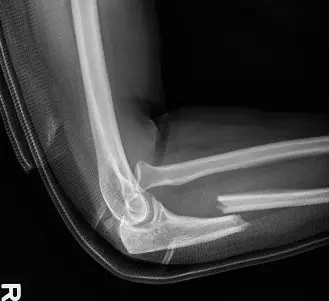

يُعد كسر مونتيجيا (Monteggia fracture-dislocation) إصابة معقدة ونادرة نسبيًا تصيب منطقة الساعد والمرفق، وتتطلب فهمًا عميقًا وتشخيصًا دقيقًا وعلاجًا متخصصًا لضمان أفضل النتائج للمرضى. هذه الإصابة، التي وصفها الجراح الإيطالي جيوفاني باتيستا مونتيجيا لأول مرة عام 1814، تتميز بوجود كسر في عظم الزند (الذي يمتد من المرفق إلى الرسغ) مصحوبًا بخلع في رأس عظم الكعبرة (الذي يقع عند المرفق).

على الرغم من أن كسور مونتيجيا أكثر شيوعًا عند الأطفال، إلا أنها عندما تحدث عند البالغين، فإنها غالبًا ما تكون نتيجة لصدمات عالية الطاقة، مما يجعلها أكثر تعقيدًا وتحديًا في العلاج. تشكل هذه الإصابات تحديًا كبيرًا للأطباء بسبب طبيعتها غير المستقرة وميلها الكبير إلى النتائج السيئة إذا لم يتم التعامل معها بشكل صحيح وفوري. في صنعاء، يقدم الأستاذ الدكتور محمد هطيف ، استشاري جراحة العظام والعمود الفقري، خبرته الواسعة في تشخيص وعلاج حالات كسر مونتيجيا المعقدة، مستخدمًا أحدث التقنيات لضمان أفضل فرص الشفاء للمرضى.

الأشعة السينية العادية (Plain Radiographs):

- الصور الأمامية والخلفية والجانبية للساعد بأكمله، بما في ذلك المرفق والرسغ: هذه الصور حاسمة للتشخيص. الصورة الجانبية ضرورية لتقييم العلاقة بين رأس الكعبرة واللقمة العضدية. يجب أن يقطع خط يمر عبر مركز رأس الكعبرة دائمًا اللقمة العضدية في جميع المناظر والأوضاع. الفشل في ذلك يشير إلى وجود خلع.

- الصور المائلة: يمكن أن تساعد في تحديد أنماط الكسر، خاصة التفتت.

- صور المرفق المقابل: مفيدة للمقارنة، خاصة في حالات الاشتباه في خلع خلقي لرأس الكعبرة أو إصابة سابقة.